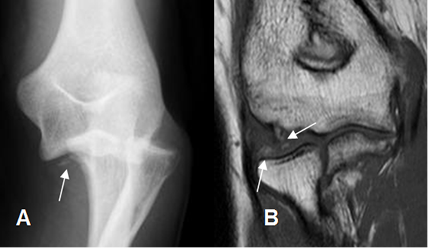

Fig 34. Luxofractura del radio, con cuerpos libres.

A: Rx AP. Luxación del radio, con cuerpos libres.

B: RM coronal en T1. Radio reducido, con cuerpos libres intra-articulares.